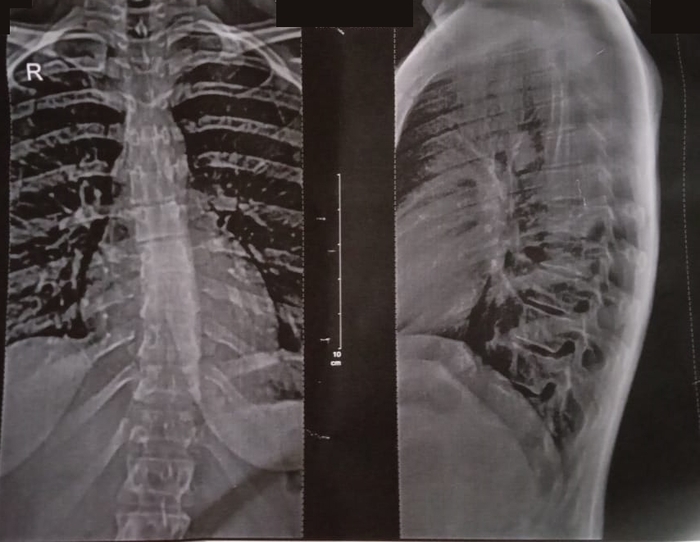

Привезли парня с стройки, упал с высоты. Средняя Азия, русский почти не знает. Сломал 8-й грудной позвонок, ниже поясницы ничего не чувствует, ноги не работают. Мочеиспускание только через катетер, стул отходит самопроизвольно.

Сделали всё, что могли: сложная операция, репозиция, декомпрессия, поставили восемь винтов. Технически всё прошло хорошо.

Но самое грустное — мы знали результат ещё до того, как начали. Спинной мозг не восстановить. Этот сильный, молодой парень навсегда останется прикованным к креслу. Сказать честно, я не стал ему говорить про то что он не будет ходить, вести половую жизнь и тд. Тут лучше оставить лучик надежды.